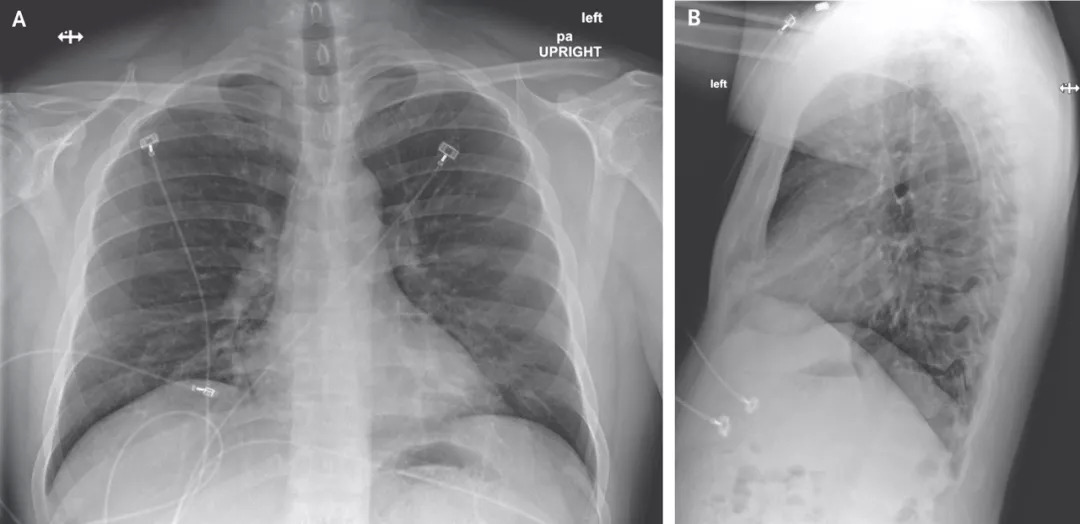

图一:后胸部和外侧胸部X光片